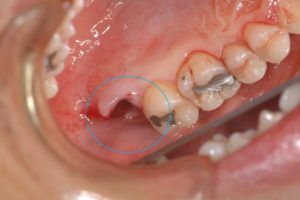

上顎の親知らず(青〇)を抜歯しました。

抜歯した親知らずを移植して縫合しました。特別な固定は不要です。

親知らずはこのように移植することも可能です。そのため、保存できる親知らずは抜歯する必要はありません。

また、親知らずの抜歯は保険適応です。今回の症例も保険診療で行っています。